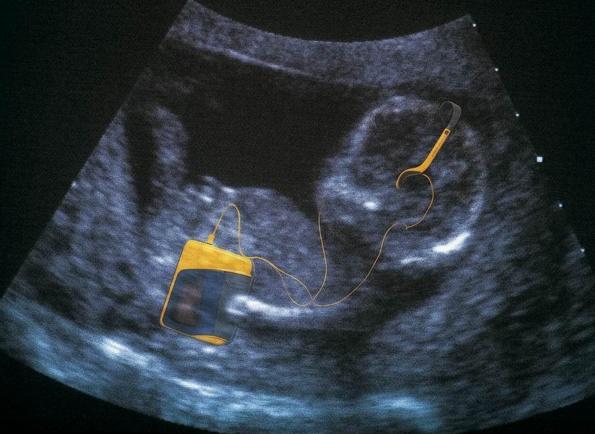

1、超声波扫描:超声波是一种声波,到目前为止的报告显示,它对胎儿没有不良影响,因此在妇产科界使用非常普遍。利用超声波诊断胎儿性别时,男婴的准确度可达95%以上,女婴的可靠度则只有85%左右。而且准确度还是B超师或者医生的经验有直接的关系